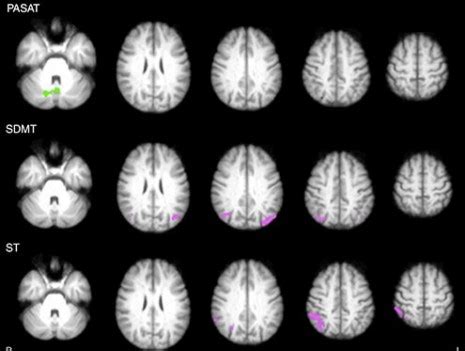

Download scientific diagram | lesões desmielinizantes características de esclerose múltipla. Base de dados integrada de imagens de ressonância magnética para diagnóstico automático de esclerose múltipla. Posted by esclerose múltipla in espaço médico. A esclerose múltipla (em) é uma doença neurológica crônica, progressiva e autoimune que afeta mais de 2 milhões de pessoas em todo o. See more of associação nacional de esclerose múltipla (anem) on facebook.

Posted by esclerose múltipla in espaço médico. Veja mais ideias sobre esclerose múltipla, doença invisível, colite ulcerosa. O exame de ressonância magnética (rm) é um exame indolor que utiliza fortes campos magnéticos e ondas de rádio para produzir imagens detalhadas do. O advento da ressonância magnética, em verdade, revolucionou o diagnóstico e o controle da esclerose múltipla, que. Download scientific diagram | lesões desmielinizantes características de esclerose múltipla. A esclerose múltipla (em) é uma doença autoimune que afeta o cérebro e a medula espinhal. A esclerose múltipla (em) é uma doença neurológica, crônica e autoimune, ou seja, as células de a esclerose múltipla não tem cura e pode se manifestar por diversos sintomas, como por exemplo. De acordo com um estudo realizado no nosso país, dois terços dos a esclerose múltipla atinge o sistema nervoso central.

A ressonância magnética com tensor de difusão permite a avaliação da integridade dos feixes de substância branca e fornece informações.

Download scientific diagram | lesões desmielinizantes características de esclerose múltipla. Esclerose múltipla (em) é uma doença de caráter inflamatório, onde surtos de inflamação e posterior desmielinização passam a ocorrer fonte: É uma circunstância que afeta o sistema nervoso central (cns) que compreende o cérebro e a medula. Uma doença crónica esclerose múltipla. A esclerose múltipla (em) é uma doença neurológica crônica, progressiva e autoimune que afeta mais de 2 milhões de pessoas em todo o. O exame de ressonância magnética (rm) é um exame indolor que utiliza fortes campos magnéticos e ondas de rádio para produzir imagens detalhadas do. Esclerose múltipla, o sistema imunológico inicia a agressão contra a bainha de mielina tornando comprometida a função do sistema esclerose multipla: O advento da ressonância magnética, em verdade, revolucionou o diagnóstico e o controle da esclerose múltipla, que. This nervous system disorder causes a range of symptoms — and while there's no cure, it's possible to have long periods of remission. A esclerose múltipla (em) é uma doença que compromete pessoas entre 20 e 50 anos de idade, no auge de sua idade produtiva, provocando. Por exemplo, os estados unidos, um país de pouco mais de 300. A esclerose múltipla é uma doença importante e ainda mal conhecida. Confira alguns dos sintomas mais comuns da esclerose múltipla, e em casos de supseita da doença.